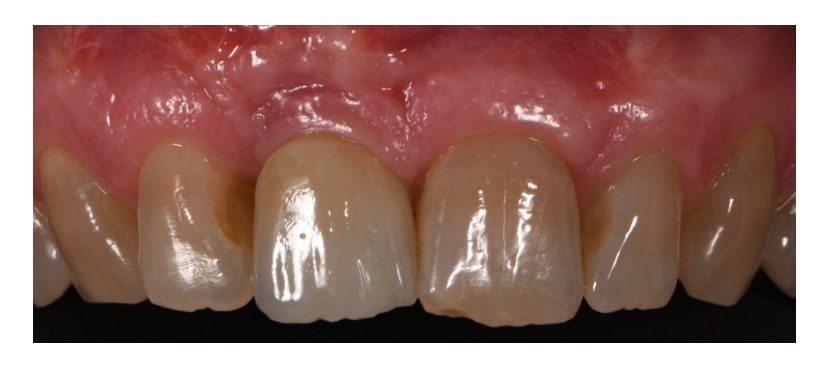

In both groups, six to eight months after tooth extraction (group A and B, respectively), dental implants (Premium, Sweden and Martina, Due Carrare, PD, Italy) were placed. In none of the cases was it necessary to carry out an additional GBR. The amount of bone was judged sufficient to place an implant of 3.8 mm of diameter and 10 to 11.5 mm of length. Flap design was performed according to the clinical scenario and the patient’s requirements. Before implant site preparation, a calibrated trephine bur with a 3.0 mm external diameter was used to collect a core sample for histologic analysis. The implants were submerged for three months. Three months after implant placement, a screw-retained temporary restoration was delivered. Finally, two to three months after initial loading, a definitive, screw-retained, CAD/CAM, metal-free restoration was delivered. Occlusion was adjusted, and follow-up visits were scheduled every four months.

No implant failure and no complications were experienced. In addition, all the patients were fully satisfied with the function and aesthetic of their implant-supported restoration, and no differences were experienced in their perception of the therapy, so all the patients would undergo the same therapy.